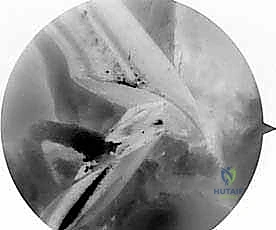

- الجراحة المجهرية وتنظير المفاصل بدقة 4K: يستخدم الدكتور هطيف أحدث تقنيات مناظير الركبة (Arthroscopy) المزودة بكاميرات عالية الدقة 4K، مما يتيح له رؤية أدق التفاصيل داخل المفصل، وتشخيص الأضرار المجهرية، وإجراء الجراحة بأقل تدخل جراحي ممكن (Minimally Invasive).

* التصوير بالرنين المغناطيسي (MRI): يوفر صورة مفصلة للأنسجة الرخوة. يحدد حالة الطعم المزروع سابقاً (هل هو ممزق، متآكل، أم سليم ولكنه غير فعال؟)، ويقيم حالة الغضاريف الهلالية والمفصلية.

* الأشعة المقطعية (CT Scan): في حالات الفشل الجراحي، تعتبر الأشعة المقطعية السلاح الأهم. فهي توفر نمذجة ثلاثية الأبعاد (3D) دقيقة جداً لمواقع الأنفاق العظمية القديمة وحجمها، مما يساعد الدكتور هطيف في اتخاذ قرار حاسم: هل يمكن حفر أنفاق جديدة فوراً، أم يجب إجراء الجراحة على مرحلتين؟